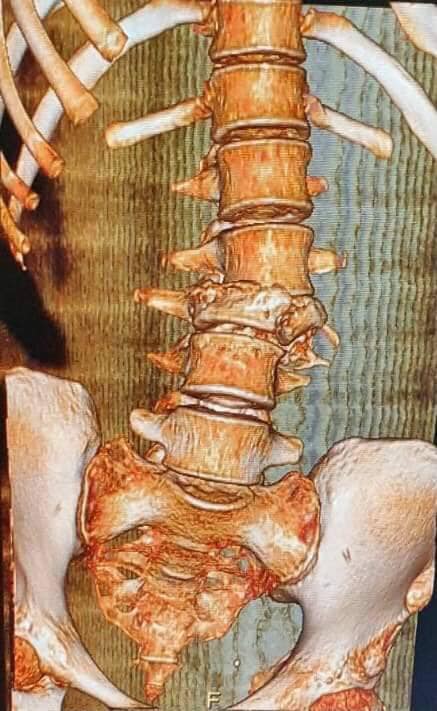

Сразу после этого пациенту провели операцию на позвоночнике, закрепив позвонки на безопасном расстоянии для реабилитации в таком положении, чтобы они не раздавили костный мозг.

"Наши специалисты провели протезирование тела позвонка путем установления распорного телескопического кейджа - импланта с его фиксацией с помощью специальных винтов. Этот винт удерживает один позвонок над другим на определенном расстоянии, позволяет сохранить опорно-двигательную функцию позвоночника и уберечь спинной мозг от сжатия", - добавили медики.